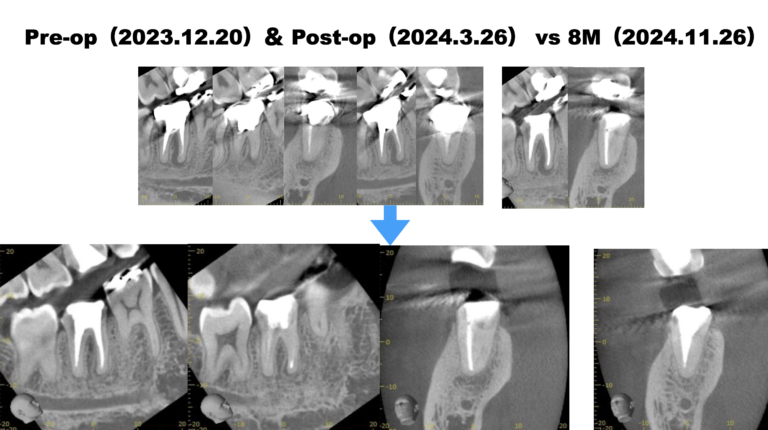

PA(2023.12.20)

近心根に根尖病変が見える。

そして、ほとんど根管形成はなされていない。

CBCT(2023.12.20)

MB

根切するには厳しい位置に#31のM根のApexはある。

穿通は必須である。

ML

MLには根尖病変と思しき透過像がそれほど顕著ではないが若干見える。

そして、生活歯髄療法の負の遺産がこの歯牙には発生している。

そう、

根管の石灰化

だ。

その歯に根尖病変ができている。

そして、Sinus tract。

この歯を根切することは容易であろうか?

といえば、

このCT画像が語っていることは、

頬側の皮質骨は相当厚いという臨床的事実だ。

それがApicoectomyを困難にしているのだろう。

#30 Re-RCT(2024.3.26)

MLは石灰化が亢進している。

穿通するだろうか?というよりも、ProTaper SXでコロナルフレア形成できるだろうか?

ともかく、SXを使用するにはそれが入る道を作らねばらない。

短針で、スカウティングした。

その後、SXを使用したが

SXでコロナルフレア形成はできなかった。

そのような時、どうするべきだろうか?

といえば、

どうもできないのである。

つまりこの時点で、

MLは形成が不可能である

という事実がわかる。

MBのみの根管再形成に着手して根充した。

術後にPA, CBCTを撮影した。

MLは石灰化が亢進しており何もできなかった。

これで治癒するか?は神様が決めることである。